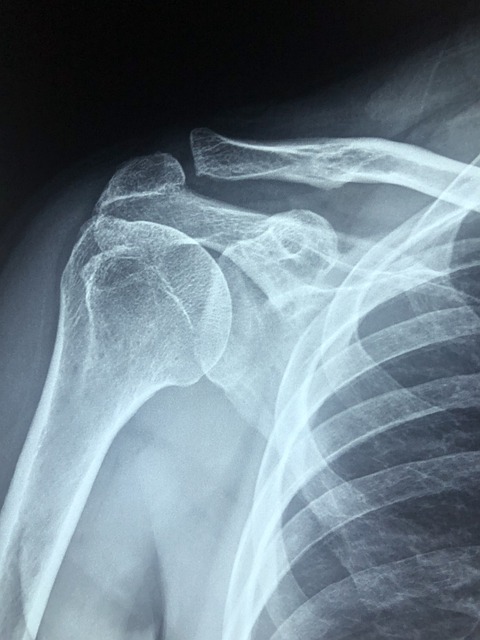

어깨 부위와 오른쪽 팔 상단 쪽을 엑스레이 촬영을 하고 그 부분을 함께 보여주셨습니다. 엑스레이에는 어깨 부위에 뿌옇게 뭔가 보였는데 그게 석회라고 하셨습니다. 석회 덩어리가 커져서 어깨를 회전할 때마다 근육을 찔러 통증을 유발한다고 말씀하셨습니다.

일반적으로 뼈에서는 석회가 원래 나오고 나왔던 석회가 다시 뼈로 흡수되는 과정이 반복되는데 그 과정 중에 석회가 남고 흡수가 잘 안 될 경우 석회가 뭉쳐서 통증을 유발한다고 합니다. 사실 이렇게 뭉친 석회는 쉽게 흡수가 이루어지지 않지만 결국 아주 오랜 시간이 지나면 자연 흡수도 가능하다고 합니다. 다만 그동안 발생하는 통증이 문제인 것입니다.

첫 엑스레이에서 덩어리로 보이던 석회는 작은 조각으로 바뀌어 있었습니다. 의사 선생님께서는 여기서 체외 충격파를 해도 더 이상 사이즈가 줄어들 것 같지도 않고 조각이 충분히 작아졌으니까 이대로 자연스럽게 뼈로 흡수될 것이라고 알려 주셨습니다.